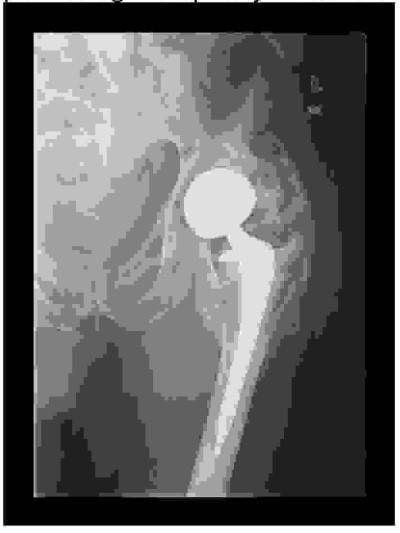

Wskaż stopień skostnienia pozaszkieletowego widoczny na radiogramie po zabiegu alloplastyki stawu biodrowego wg klasyfikacji Brookera:

Pytanie 79

Przedstawiony radiogram wykazuje zmiany zwyrodnieniowe stawu biodrowego powstałe w wyniku: